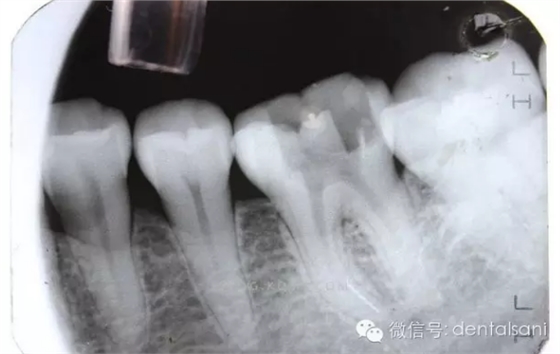

折斷器械的取出根管治療過程中可能會(huì)發(fā)生器械折斷,影像根管的通暢、預(yù)備和完善充填,導(dǎo)致治療失敗。因此,根管內(nèi)異物取出或者是通過是必要的。臨床上有多種根管內(nèi)折斷器械的取出方法,包括超聲、H銼、套管和根尖手術(shù)等。

(1)通路建立:臨床操作中,X線明確斷針位置后,在根管顯微鏡(放大10~20倍)觀察下,先用帶柄根管銼插入根管,直到斷針冠方斷面,用止動(dòng)片標(biāo)記,確定斷針深度。然后用K銼或者H銼將斷針上部的根管預(yù)備到30~40#,將GG鉆2#和3#尖端磨平,使GG鉆尖端平面的直徑大于斷針的直徑,用2?;蛘?#調(diào)磨后的GG鉆從根管口預(yù)備到斷針的位置,建立通道,使斷針以上部分根管明顯通暢,便于顯微鏡觀察和術(shù)中操作。

首先,是斷針?biāo)幐苌疃龋瑱M截面直徑和根管彎曲度。一般情況下,如果能暴露折斷器械長(zhǎng)度的1/3,??梢匀〕觯蝗绻蹟嗥餍堤幱诒容^直的根管中比較容易取出;如果折斷器械部分處于根管彎曲處,并且牙本質(zhì)厚度容許建立從根管口到器械冠方的通道,斷針也是可能被取出的:但是如果斷針處于根管彎曲處以下至根尖區(qū),則是很難建立安全的通道,折斷器械很難取出。